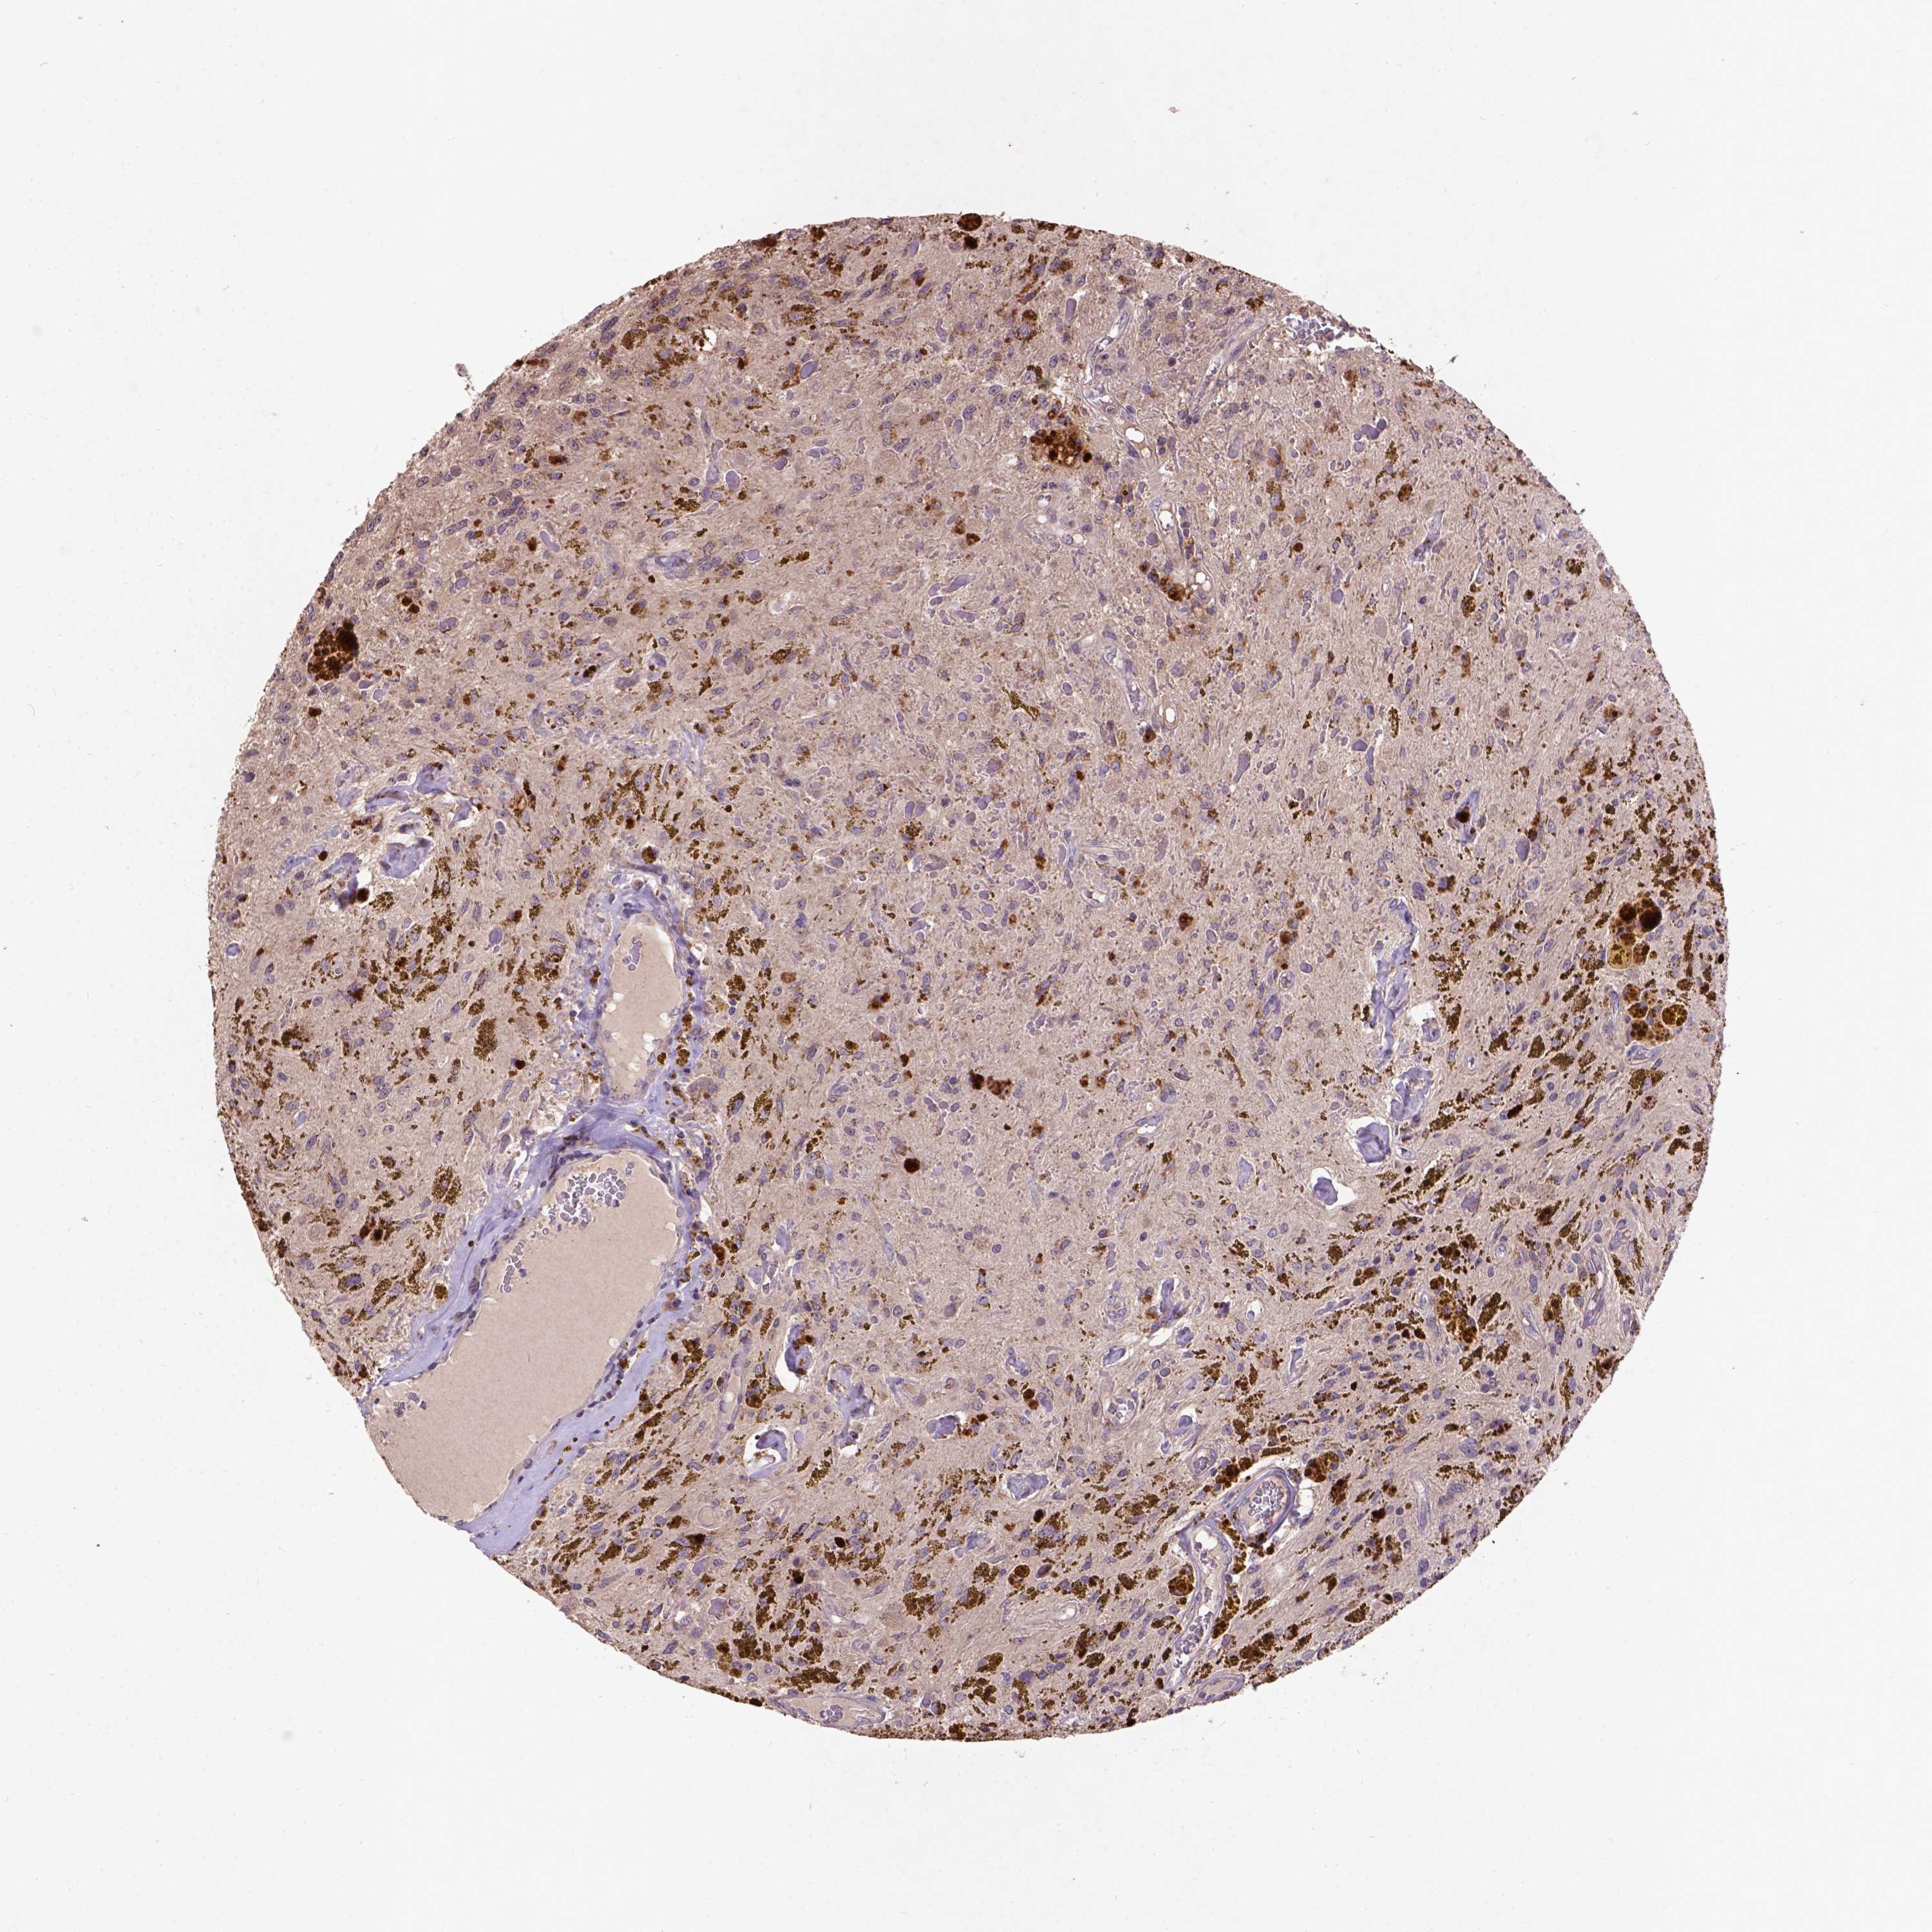

GLIOMA - Protein expressioni

A mouse-over function shows sample information and annotation data. Click on an image to view it in a full screen mode. Samples can be filtered based on level of antibody staining by selecting one or several of the following categories: high, medium, low and not detected. The assay and annotation is described here.

Note that samples used for immunohistochemistry by the Human Protein Atlas do not correspond to samples in the TCGA dataset.

Antibody stainingi

Antibody staining in the annotated cell types in the current human tissue is reported as not detected, low, medium, or high, based on conventional immunohistochemistry profiling in selected tissues. This score is based on the combination of the staining intensity and fraction of stained cells.

Each image is clickable and will lead to virtual microscopy that enables deeper exploration of all samples and also displays staining intensity scores, fraction scores and subcellular localization as well as patient and tissue information for each sample.

Antibody HPA041285

Antibody HPA069190

Staining

High

Medium

Low

Not detected

Intensity

Strong

Moderate

Weak

Negative

Quantity

>75%

75%-25%

<25%

None

Location

Nuclear

Cytoplasmic/membranous

Cytoplasmic/membranous,nuclear

Glioma, malignant, High grade

Glioma, malignant, Low grade